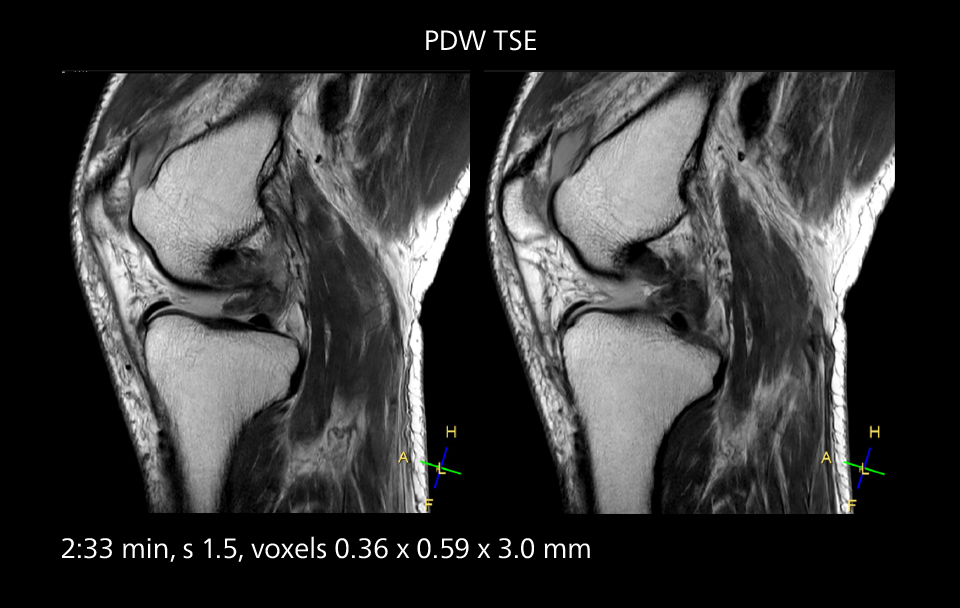

Crisp images are obtained with high resolution and short scan times using Elition X. A cyst can be seen.